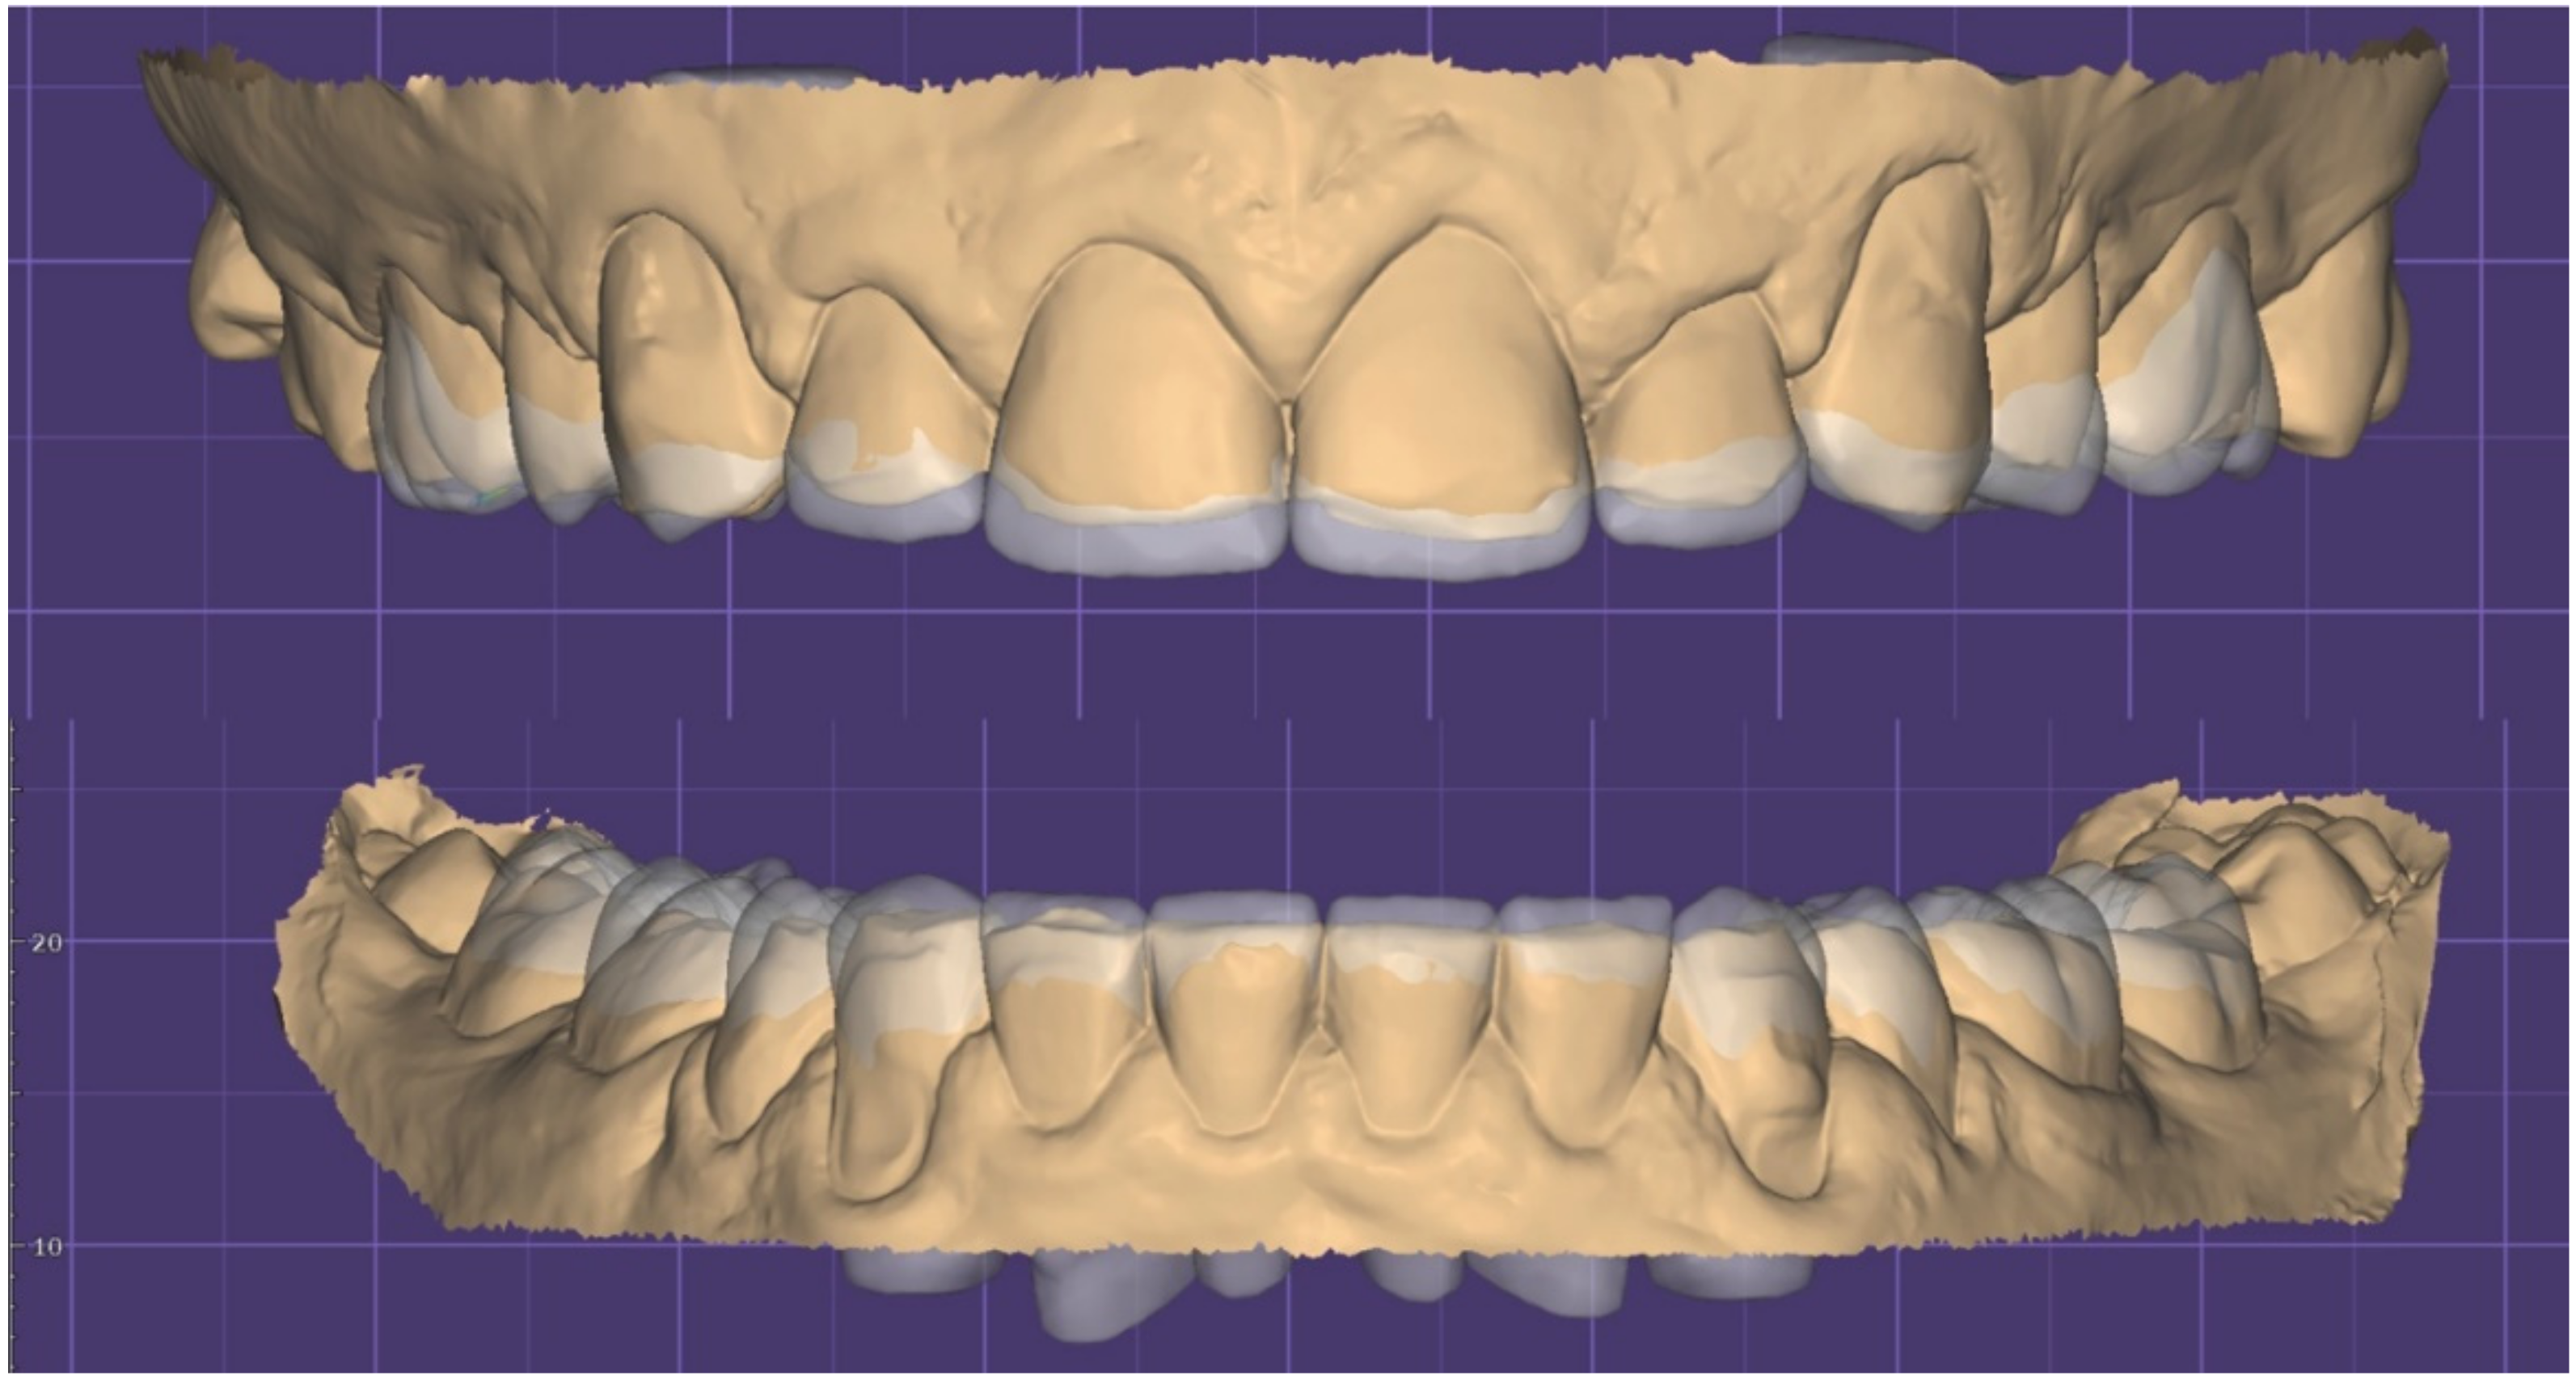

2. Clinical Report

2.1. Planning Phase

2.2. Restorative Phase